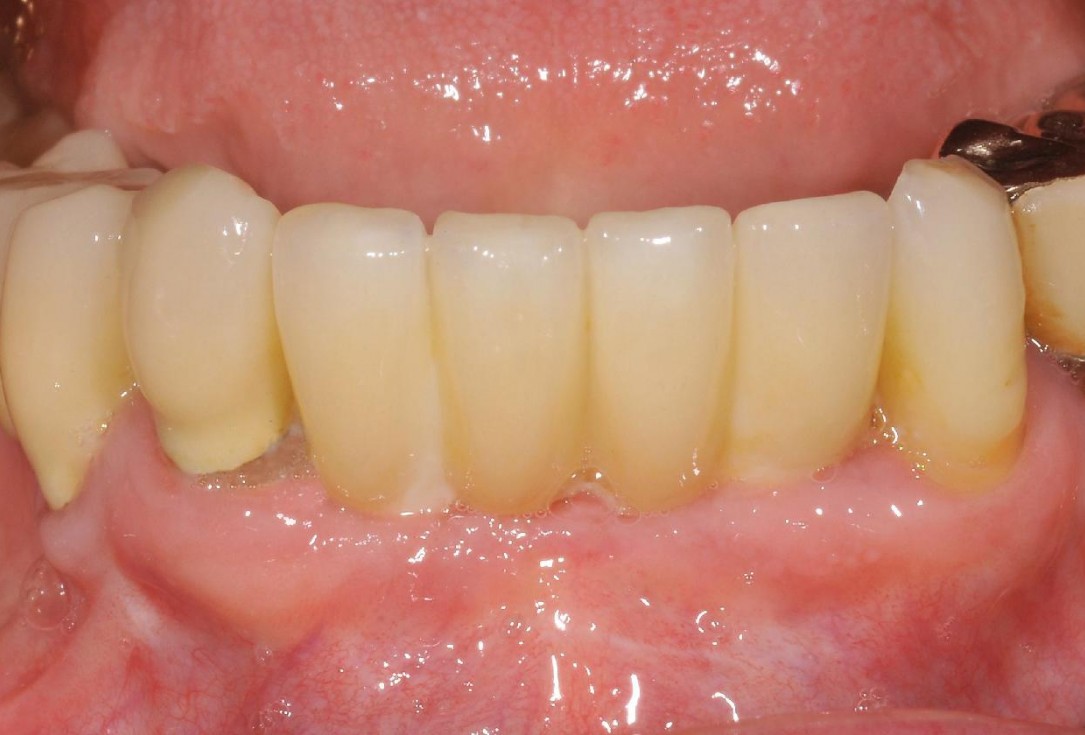

14/15 - Clincal outcome with fixed prosthesisSoft tissue augmentation and GBR with mucoderm® and maxresorb® - Dr. S. Scherg